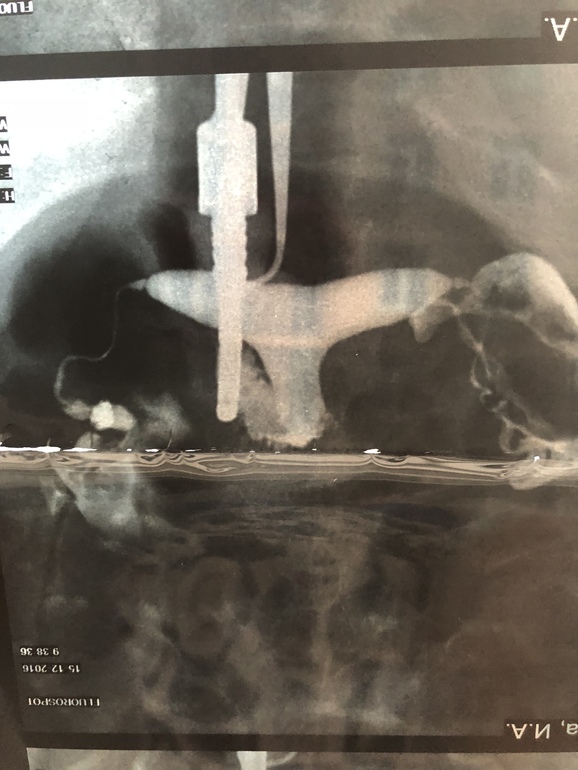

Сегодня была у врача в другой клинике, пришла на УЗИ, с полным перечнем документов и сказала, что хочу вторую попытку ВМИ. Врач посмотрел анализы, УЗИ, мрт и попросил снимок труб. По снимку сказал, у вас выход только один, ЭКО. Сказать, что я была в шоке, не сказать ничего. Ещё и муж уезжает надолго в командировку. У меня есть результат метросальпингографии в котором написано «заключение : полость матки седловидной формы, контуры четкие, ровные, отклонена кзади. Правая маточная труба визуализируеься на всём протяжении, несколько извитая, выход контраста свободный. Левая маточная труба визуализируется на всём протяжении, выход контраста свободный.»

Сказал что трубы сужены и через них не проходит яйцеклетка, ВМИ может только привести к внематочной беременности, и разрыву трубы. И выход только один, ЭКО.

Мои трубы смотрели огромное количество врачей, напротажении с декабря 2016 года и никто, ни один врач, не говорил что трубы слишком заужены. Столько времени утрачено...